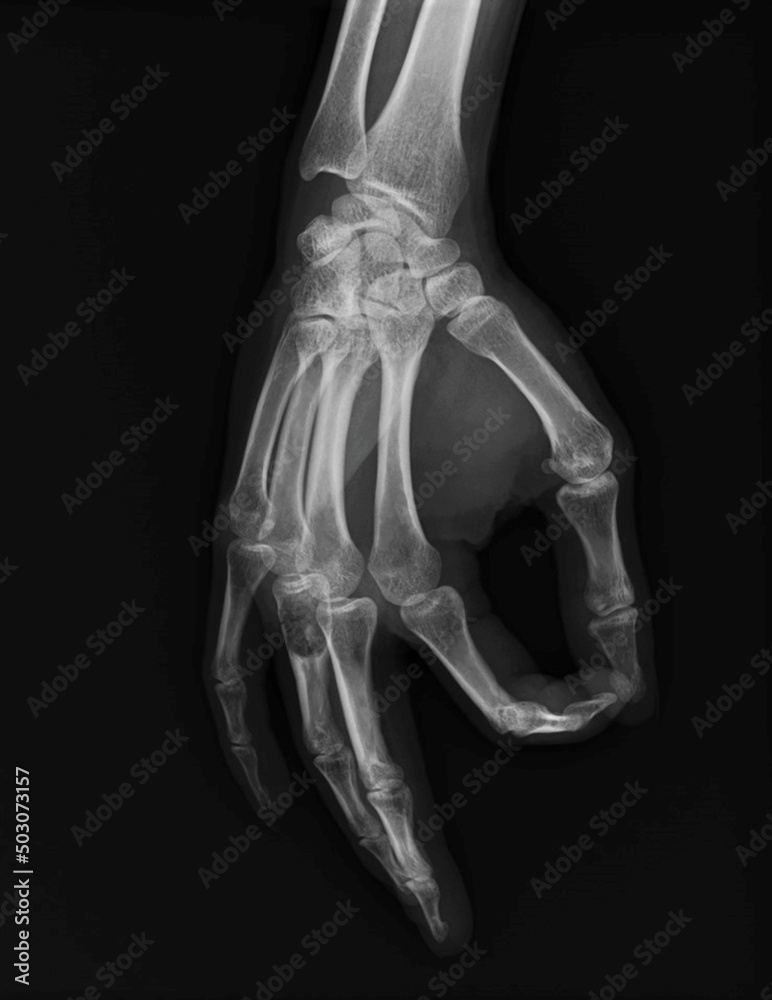

Enchondroma Hand

Enchondroma - Azouz Hand SurgeryAzouz Hand Surgery Enchondromas - Pathology - Orthobullets LearningRadiology- Enchondroma Enchondroma-of-hand LearningRadiology- Enchondroma Enchondroma Hand